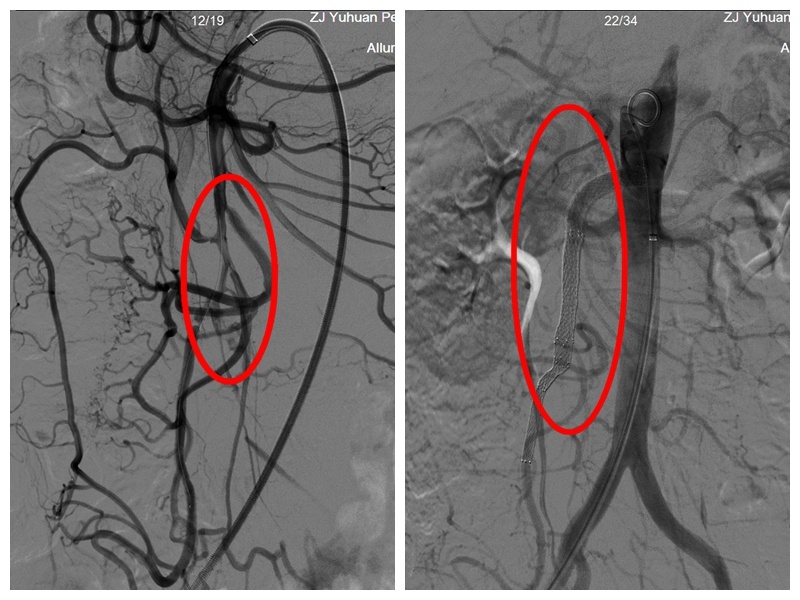

术中造影显示,肠系膜上动脉远端管腔中重度狭窄及闭塞,部分管腔充盈缺损。手术团队克服患者肠系膜上动脉长段夹层、真腔明显狭窄、动脉角度刁钻等困难,精准置入支架,即刻造影显示肠系膜上动脉狭窄消失,远端肠管供血明显改善。

左图术前造影,右图支架置入后